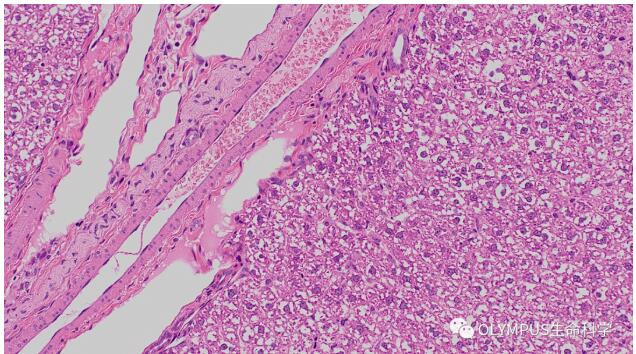

小鼠乳腺

物鏡:UPLXAPO20X

數(shù)據(jù)出處:中國科學(xué)院分子細胞科學(xué)卓越創(chuàng)新中心 曾藝組 劉春業(yè)